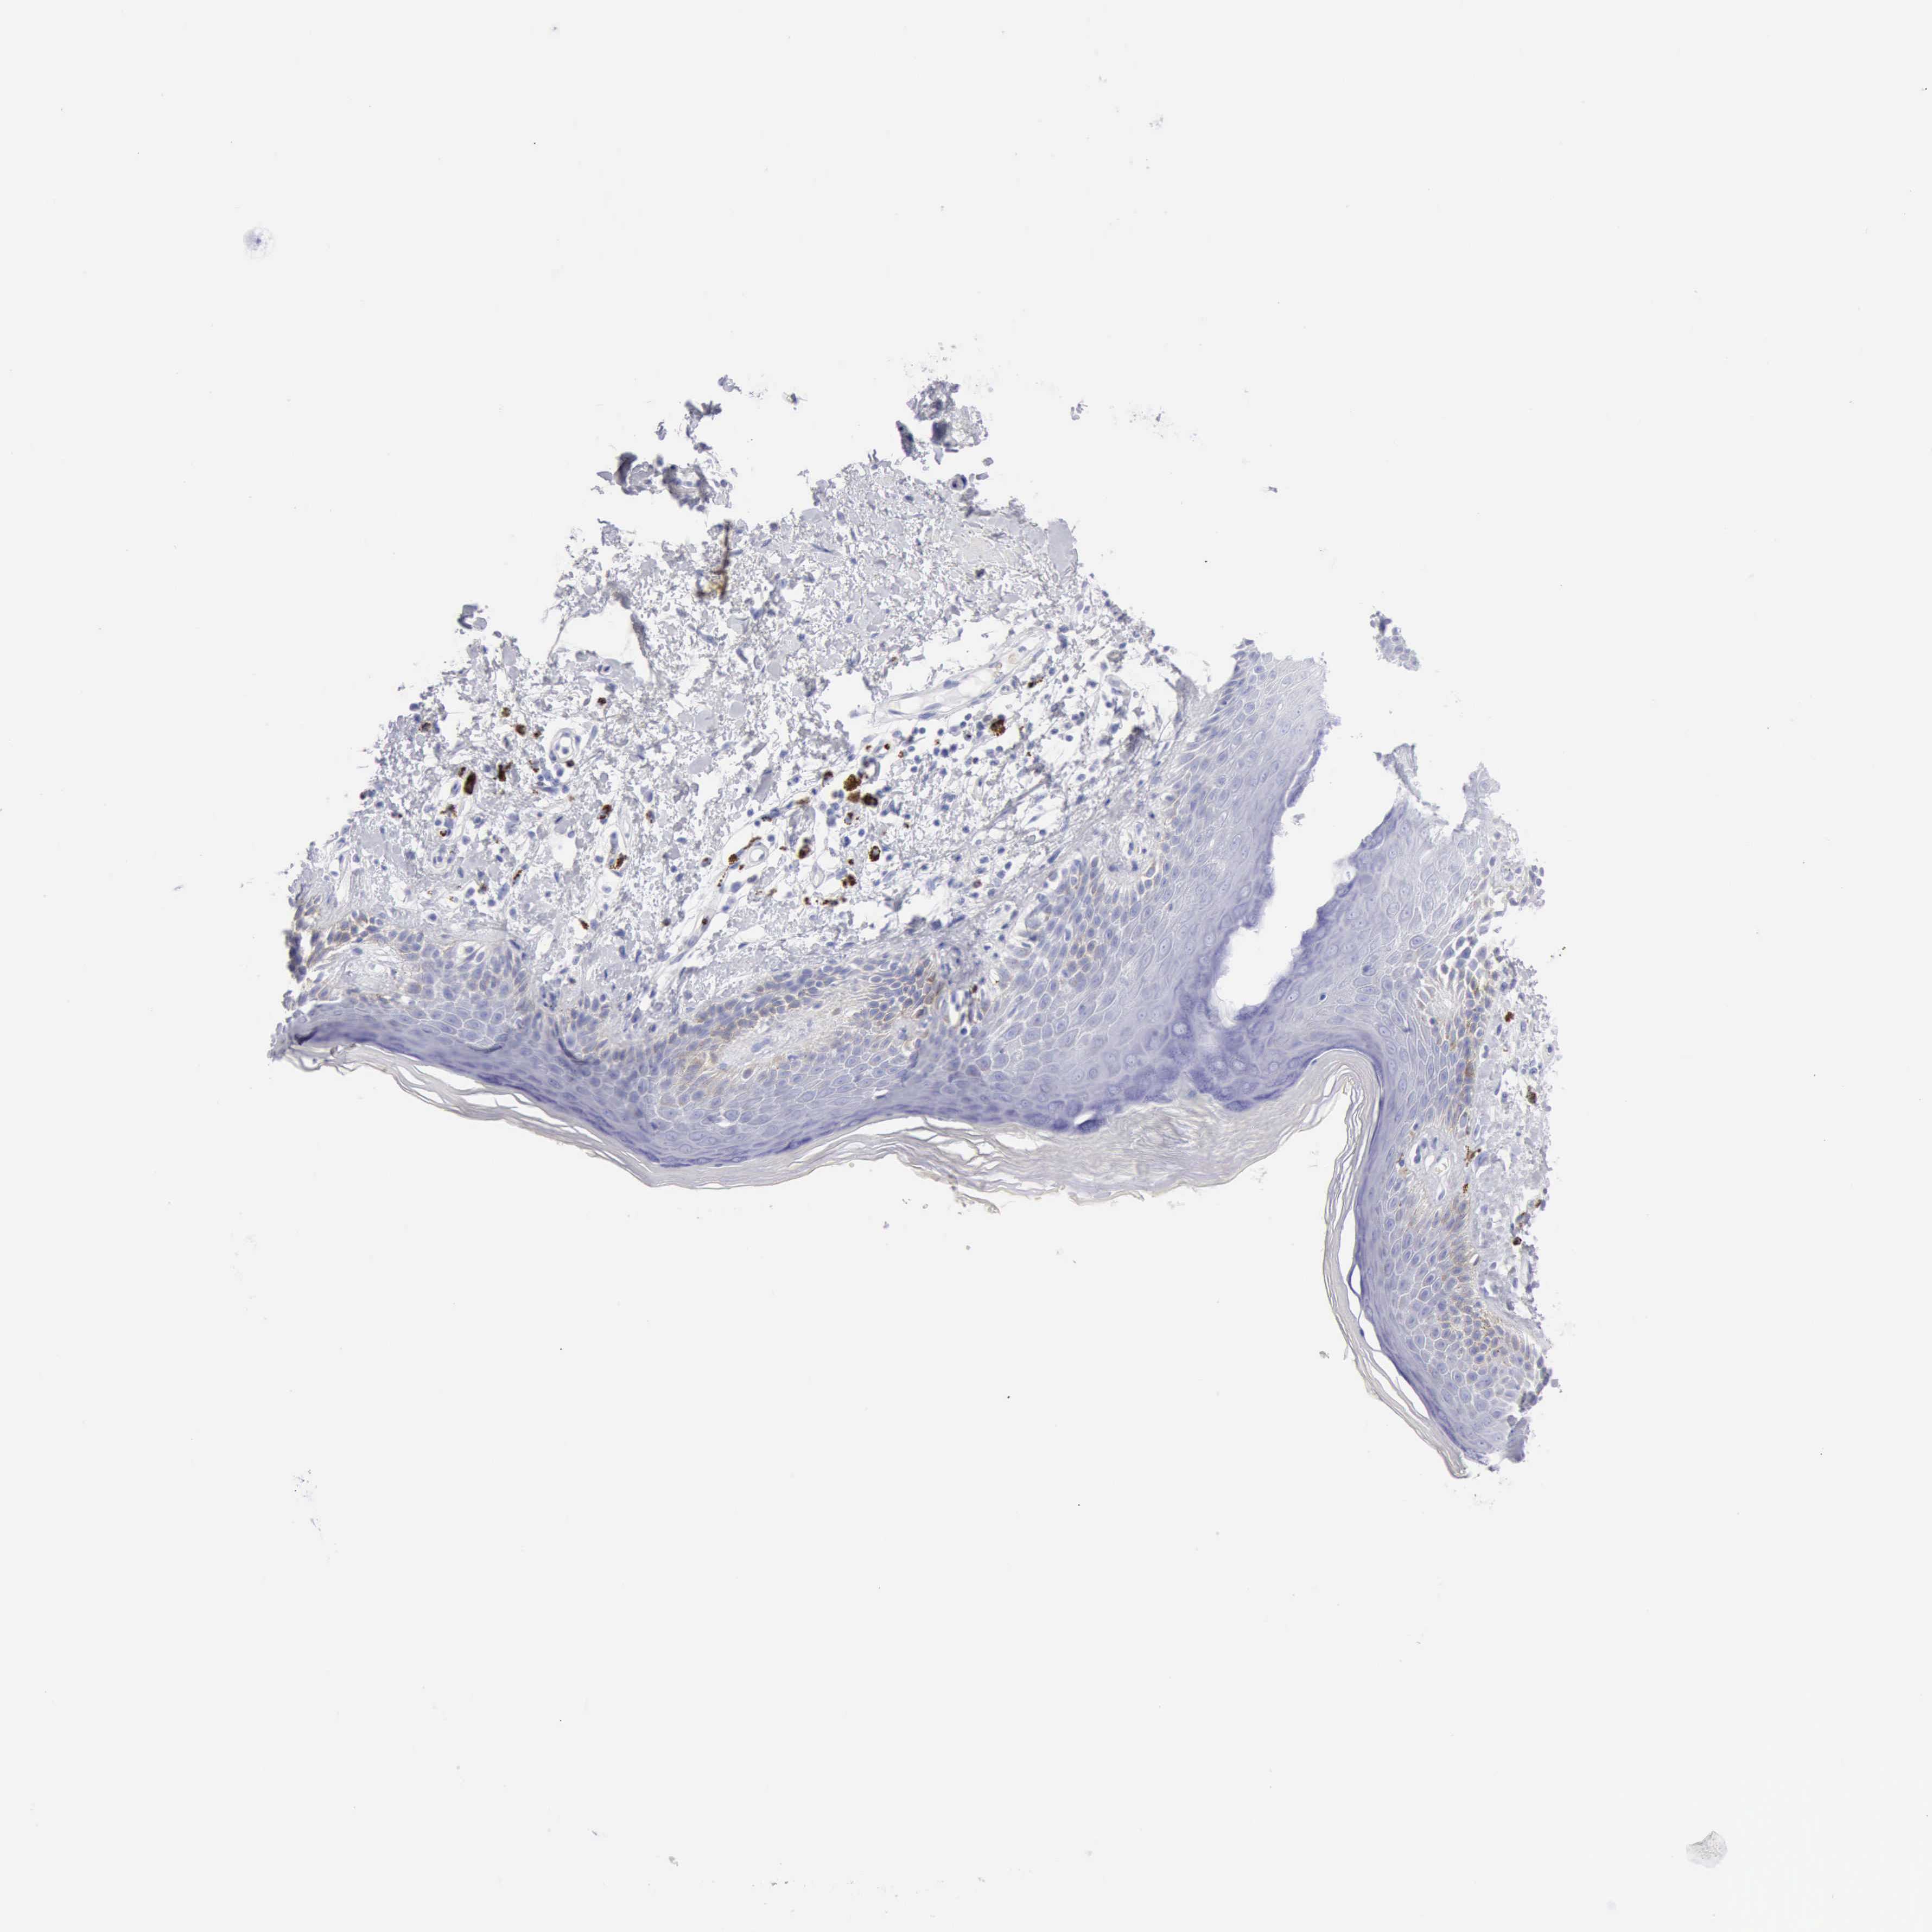

SKIN 2 - Antibody stainingi

Antibody staining in the annotated cell types in the current human tissue is reported as not detected, low, medium, or high, based on conventional immunohistochemistry profiling in selected tissues. This score is based on the combination of the staining intensity and fraction of stained cells.

Each image is clickable and will lead to virtual microscopy that enables deeper exploration of all samples and also displays staining intensity scores, fraction scores and subcellular localization as well as patient and tissue information for each sample.

Antibody HPA003418Antibody CAB000376

Cells in basal layer -Not detected

Cells in corneal layer -Not detected

Cells in granular layer -Not detected

Cells in spinous layer -Not detected

Endothelial cells -Not detected

Epidermal cells Not detected-

Extracellular matrix -Not detected

Fibrohistiocytic cells -Not detected

Langerhans cells -Not detected

Lymphocytes -High

Melanocytes -Not detected

Vascular mural cells -Not detected